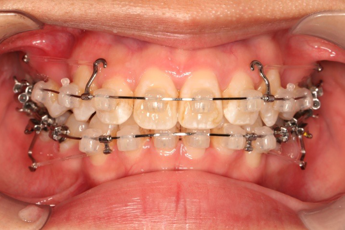

2018.11.14  术后侧面改善明显,露龈笑改善明显,笑弧笑线协调,颏部肌肉紧张度明显改善

2018.11.14  术后磨牙尖牙I类关系,中线齐,覆合,覆盖正常

宏观评价:面部对称,面下三分一比例协调,上下唇凸度正常,上颌牙列内收转矩控制良好,下颌后缩改善,颏唇沟变得更加柔和,术后达到基本直面型。

迷你观评价:上下牙齿中线与面中线对齐,笑弧协调,微笑时牙龈暴露量正常,微笑时横向正常,左右唇基本对称。

微观评价:牙齿整齐,咬合关系良好,上下前牙转矩及突度控制良好,磨牙关系I类,尖窝咬合关系良好,OB,OJ正常。